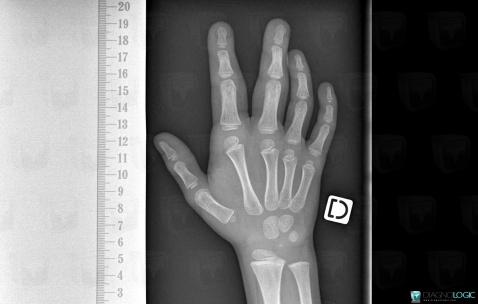

Macrodactylie, Phalanges / Os sésamoides - Main, Radio

Voici les informations spécifiques à l'image clé ci dessus:

- Diagnostic Macrodactylie, Localisation(s) Phalanges / Os sésamoides - Main, comportant les gammes